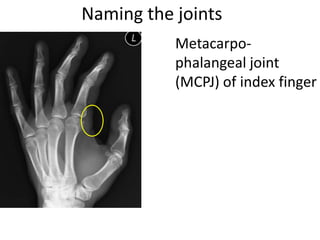

This document provides an overview of hand anatomy including:

- Naming the bones, joints, tendons, nerves and skin landmarks of the hand and wrist.